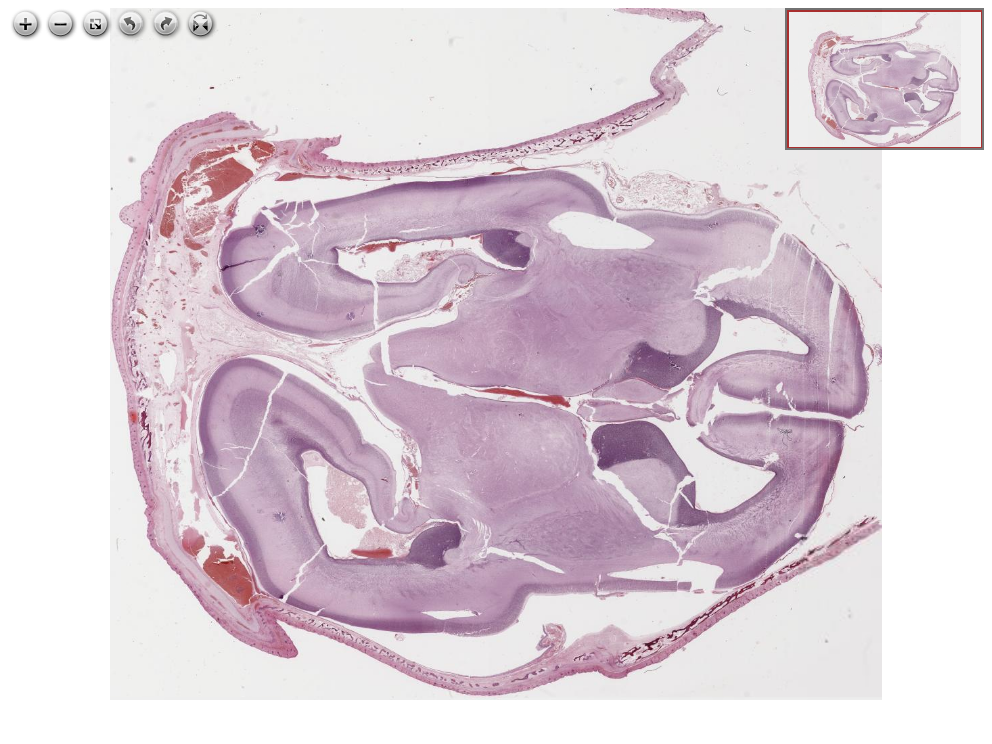

64.1 GBD Olgu 1 - pediatrik otopsi, beyin

Mikroskopik görüntüleri inceleyin: